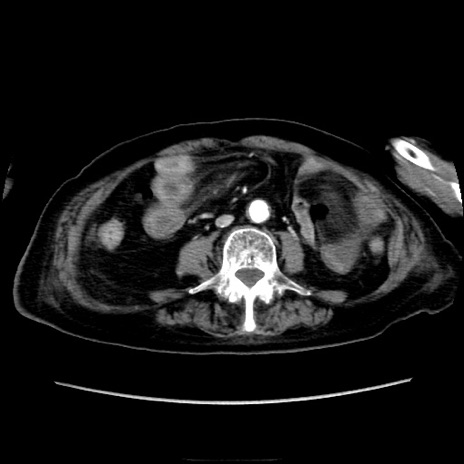

冠状断像

矢状断像